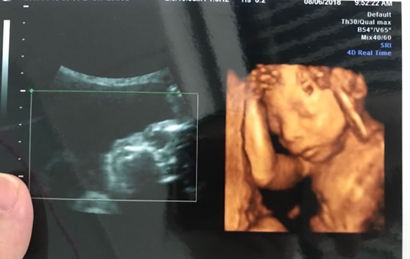

当医生正在操作B超的时分,若宝宝正处于背部的姿态或手脚正好蜷到一同,从而遮挡了性别器官,这也会形成性别的改动,另外假如你家宝宝太调皮了,不太配合,姿态不对,医生也不可以很精确的看到Ta的生殖器,结果就没有那么精确了。

胎儿在4个月的时分就能够检测到性别了,但是精确率只要85%-90%,其中男宝宝的性器官比拟明显,精确率到达95%以上,而女宝宝的性器官并没有那么明显,精确率只要85%,等胎宝宝到了28周的时分,再去检测精确率就比拟高了,简直能够到达98%-99%。